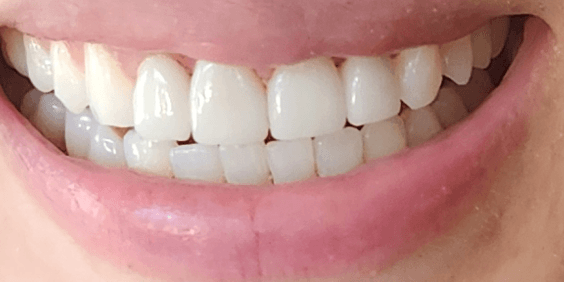

Professional clinical photography for documentation.

| Intraoral & Extraoral Photos | High-resolution clinical photography for documentation. | $100 |